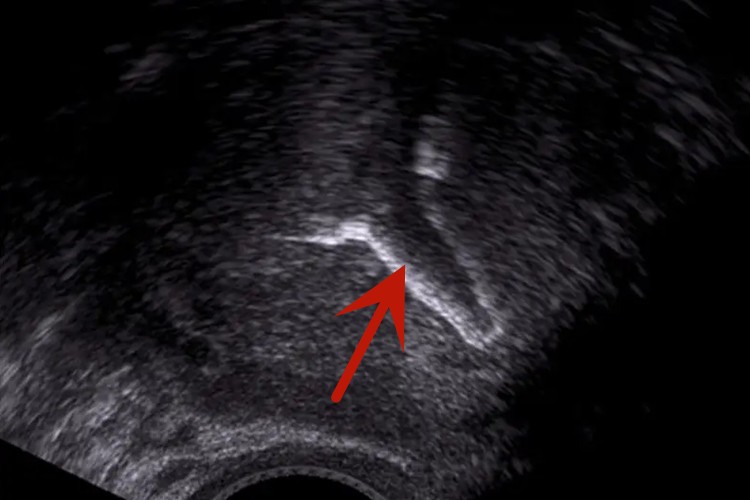

曼月乐环临床称为左炔诺孕酮宫内节育器,若已在宫内放置了这种节育器,可在彩超中显示,正常情况下,节育器的顶端接近子宫底。

曼月乐环临床称为左炔诺孕酮宫内节育器,是一种T形环,若已在宫内放置了这种节育器,通过彩超可以确定该节育器的位置。正常情况下,彩超显示宫内节育器的顶端接近子宫底,若显示宫内节育器的顶端距宫底较远,提示出现了节育器的下移。